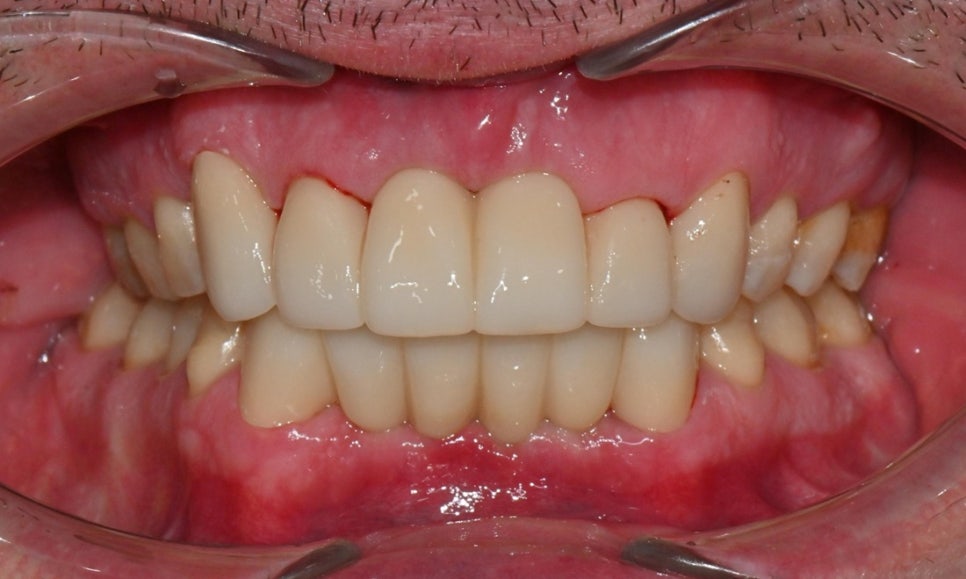

2026-1-7 최종 보철물 장착 : 연세정원치과

치료가 모두 마무리된 후, 환자분의 미소는 이전과 비교해 전반적으로 한층 더 안정적이고 조화로운 인상으로 개선되었습니다. 앞니의 길이, 형태, 배열이 아랫입술 곡선을 따라 형성되는 smile arc와 자연스럽게 조화를 이루면서, 웃을 때 과도한 긴장감 없이 부드러운 심미적 균형을 회복할 수 있었습니다. 기능적인 교합 안정성과 함께 심미적인 만족도 역시 높게 나타났으며, 환자분도 결과에 대해 매우 만족해하셨습니다.

치료 전후 미소시 사진 : 연세정원치과

앞니 심미보철은 단순히 치아 형태를 개선하는 치료가 아니라, 얼굴과 미소 전체의 조화를 고려해야 하는 치료입니다. 이번 증례에서는 진단 단계부터 임시 보철을 통한 검증, 최종 보철물 제작에 이르기까지 환자와의 충분한 소통을 바탕으로 디자인을 세밀하게 조정하였고, 그 결과 기능과 심미 모두에서 예측 가능하고 안정적인 결과로 치료를 마무리할 수 있었습니다. 환자 개개인의 조건과 니즈를 정확히 반영한 계획과 충분한 커뮤니케이션이 심미보철 치료에서 얼마나 중요한지를 다시 한번 확인할 수 있었던 케이스였습니다.